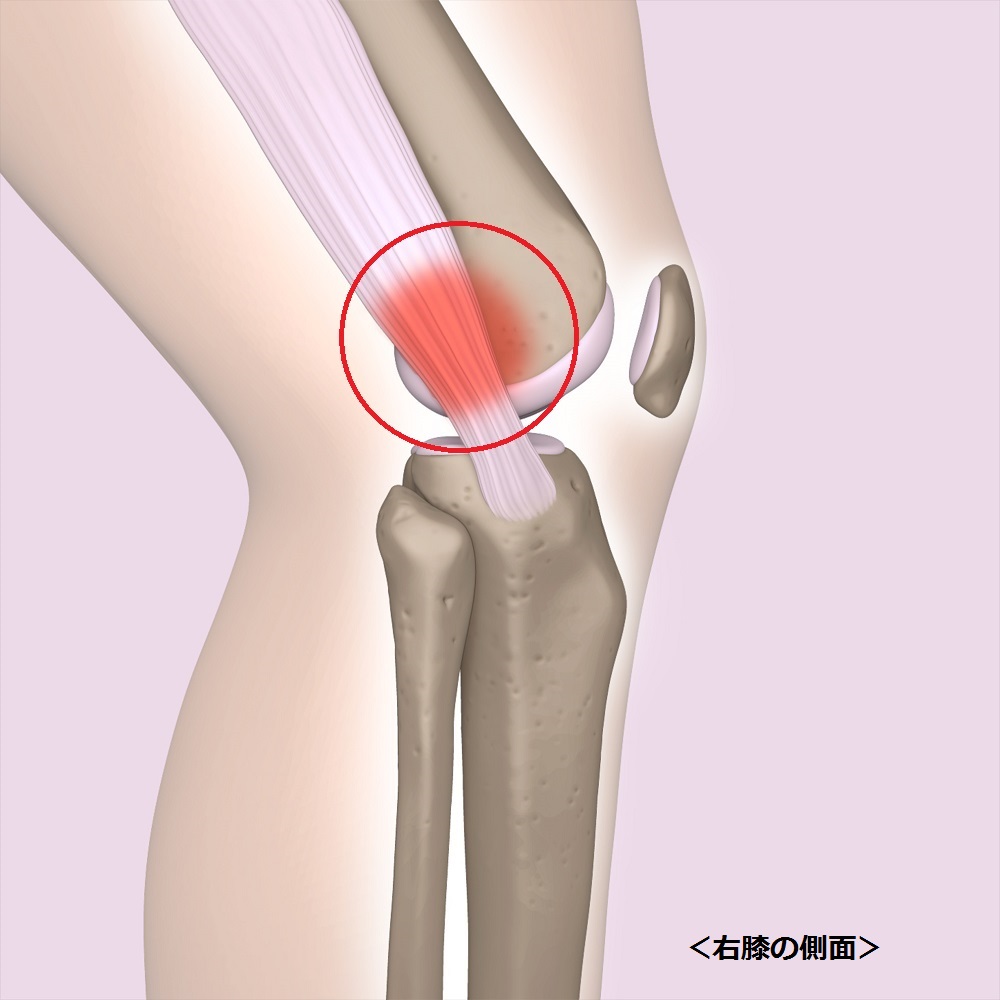

腸脛靭帯炎

腸脛靭帯炎とは、別名、ランナー膝。

マラソンなどの長距離ランナーに多く見られます。

原因は膝の屈伸運動を繰り返すことによって、

腸脛靱帯が大腿骨の外顆と言う部分と接触して炎症を起こし、

痛みが発生します。